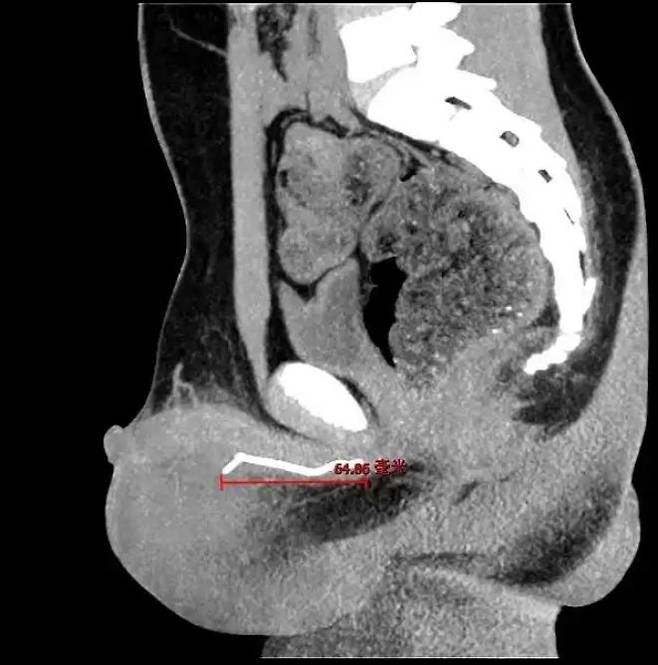

[서울=뉴시스]중국의 한 10세 소년이 하체 통증으로 병원을 찾았다가 몸속에서 7cm 길이의 철사가 발견돼 충격을 주고 있다.(사진=장강일보) *재판매 및 DB 금지

의료진은 종양 가능성을 의심해 CT 검사를 시행했고, 그 결과 소년의 요도 깊숙한 곳에서 길이 약 7cm의 철사를 발견했다.

이는 마스크 코 지지대인 것으로 밝혀졌다. 요도에서 삽입돼 음낭 부위까지 도달해 있었다.